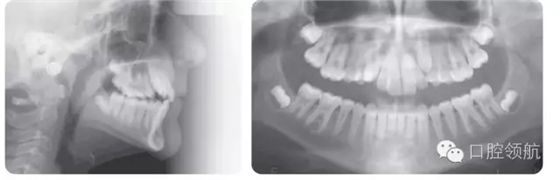

14歲男性患者,安氏I類咬合關(guān)系,輕度骨性II類長面型,嚴(yán)重的上牙列擁擠,上尖牙唇側(cè)錯位,雙側(cè)后牙反,前牙淺覆牙合(圖3.13)。